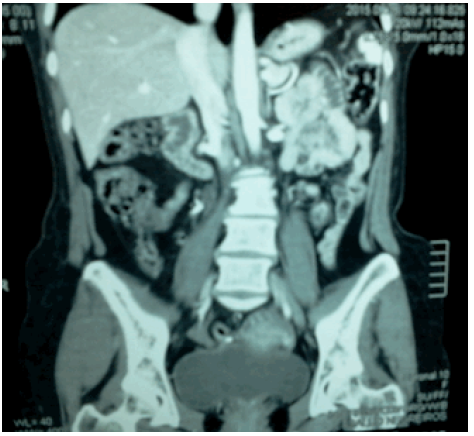

La Figura 1 corresponde a una TAC de abdomen con contraste, vesícula biliar no visible e hígado morfológicamente conservado, con presencia de imágenes de aspecto quístico subcentimétrico dispersos en el parénquima hepático, no se observan adenopatías retroperitoneales.

Fuente: Documento obtenido durante la realización del estudio.

Figura 1 Tomografia axial computarizada de abdomen con contraste.